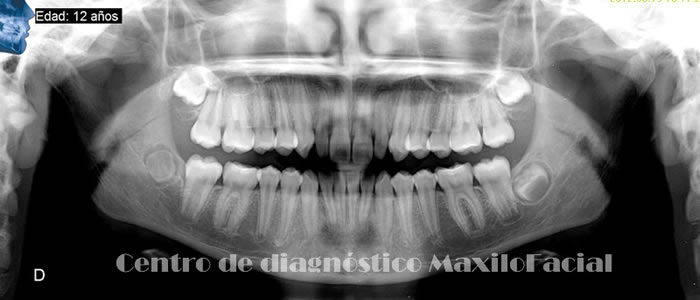

Radiografía Panorámica Dental

Permite obtener una apreciación global de los maxilares, a través de ella podemos detectar caries, enfermedad de las encías, quistes, tumores, fracturas, etc. Muchas de estas patologías son detectadas de forma casual, lo que la convierte en un estudio de protocolo a la hora de iniciar un tratamiento odontológico.

A continuación queremos mostrarle nuestra galería con algunas imágenes de casos llegados a Cedimax - Centro de Diagnóstico Maxilofacial, si requiriera más ejemplos de casos no dude en contactarse con nosotros.